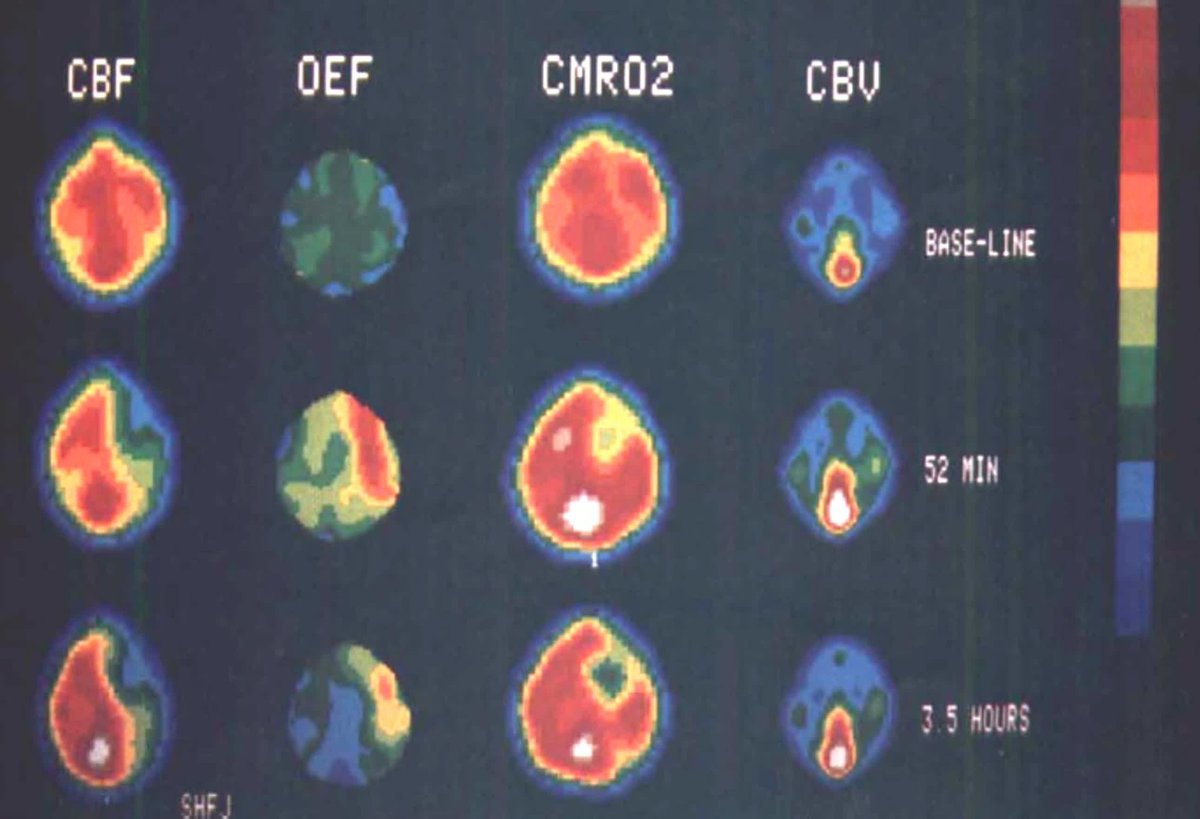

#STROKE Special Report by Baron from 2025 David G. Sherman Lecture: how PET revealed hemodynamic TIAs, validated the penumbra, showed penumbra persistence, proved patient selection matters, and uncovered selective neuronal loss. #AHAJournals ahajrnls.org/4lPYMFt